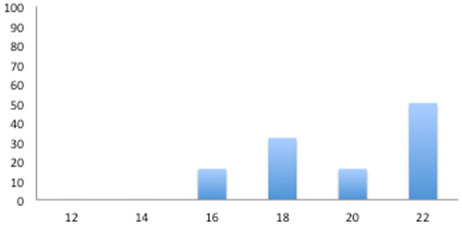

Recolheram 6 soros em intervalos de duas semanas desde a semana 12 até à 22.

Ou seja, realizou-se um teste ELISA em 36 soros dos quais 7 foram positivos, todos eles com posterioridade à semana 16.

Seroprevalência

Ou seja, que o momento de infecção podia-se situar em redor das 14 semanas, coincidindo com o caso anteriormente descrito.